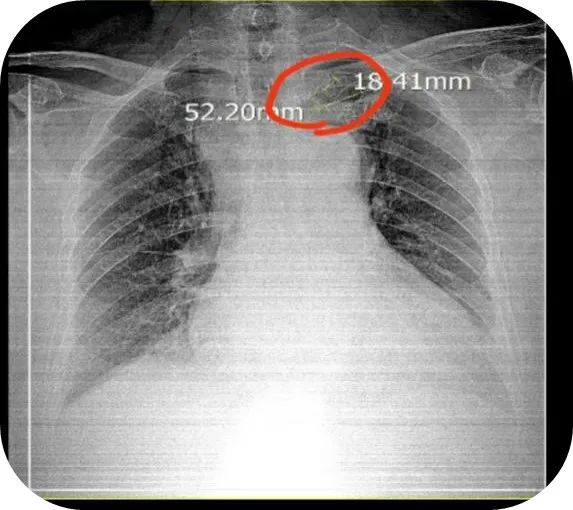

1 床王先生,入院拍摄 X 线胸片,显示 PICC 导管漂浮到颈静脉,于是特别紧张地追问小李护士……

2021 年 INS 指南中关于中心血管通路装置(CVAD)异位的概念可以分为原发性和继发性两种。其中,导管继发性异位是指 PICC 导管置入时末端位置准确,但在使用过程中导管末端位置发生移位,离开准确位置,这在导管留置的任何时间段都可能发生。异位主要发生于颈内静脉、腋静脉、锁骨下静脉等部位,其中颈内静脉异位发生率最高。这种情况我们一般可以通过 X 线胸片及时发现。